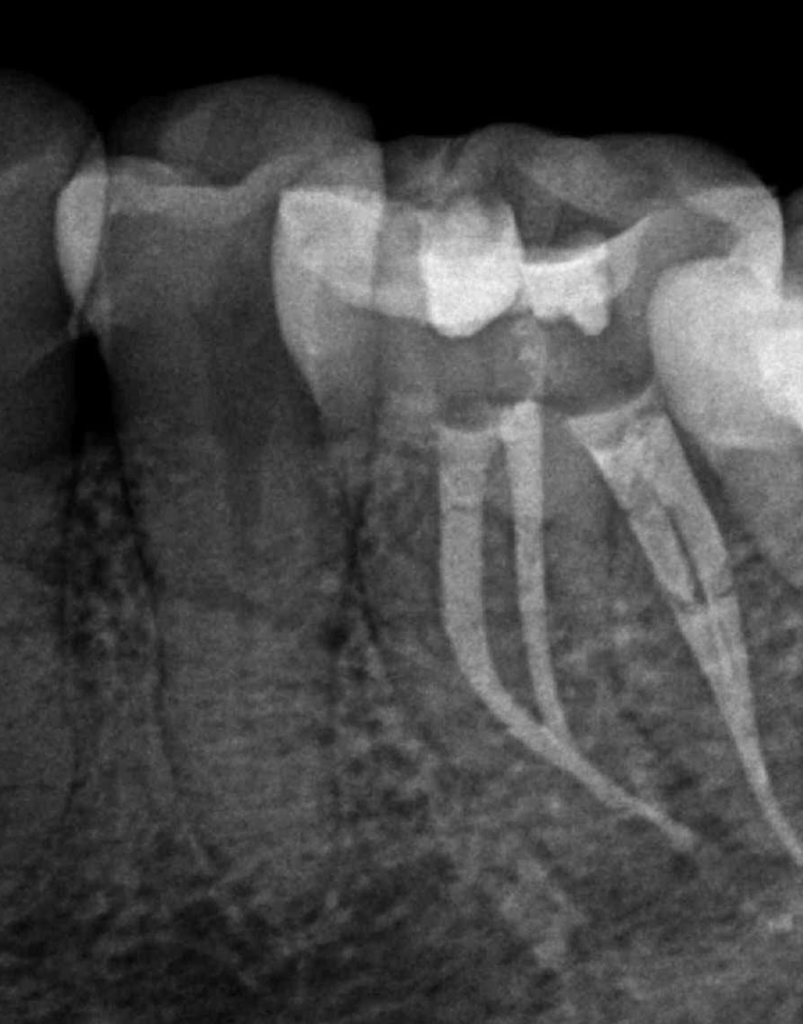

Molar inferior, conducto CM